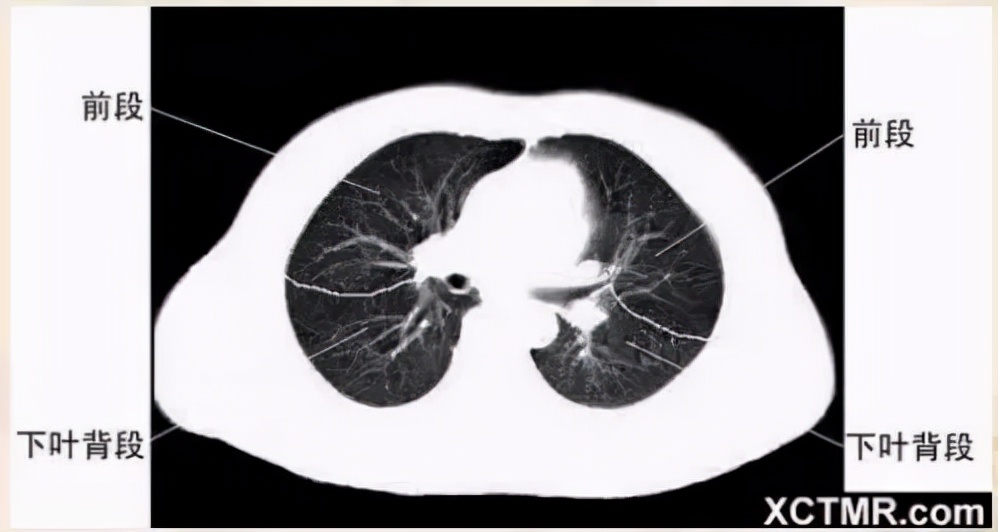

气管分叉层面

右上叶支气管层面

左主支气管层面